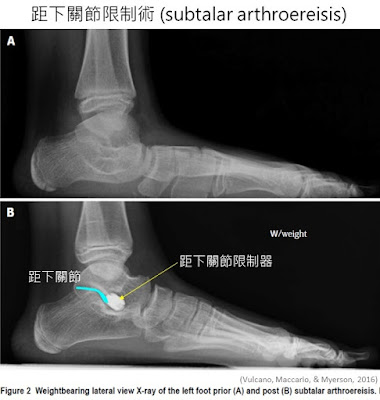

距下關節限制術是微創手術,方法是切開一個1公分的切口,將一個錐筒狀的鈦合金殖入物,利用手術中X光監視放入跗骨竇(sinus tarsi)的位置,即可矯正結構;

手術目的是為了限制距下關節過大的活動度,進而幫助維持縱足弓的位置;這個手術適合的年齡為

7-14歲(須看生長板癒合狀況,如已全癒合則預後較不好),術後到成人即可定型,若無異物感,一般不需取出殖入物;

回顧的文獻研究平均追蹤7.4年,結果都極為良好,受試者滿意度佳(good to excellent level 90%以上);患者術後即可行走,通常六週後恢復跑步,三個月後可允許接觸不規則性運動(足球、籃球、棒球等)。